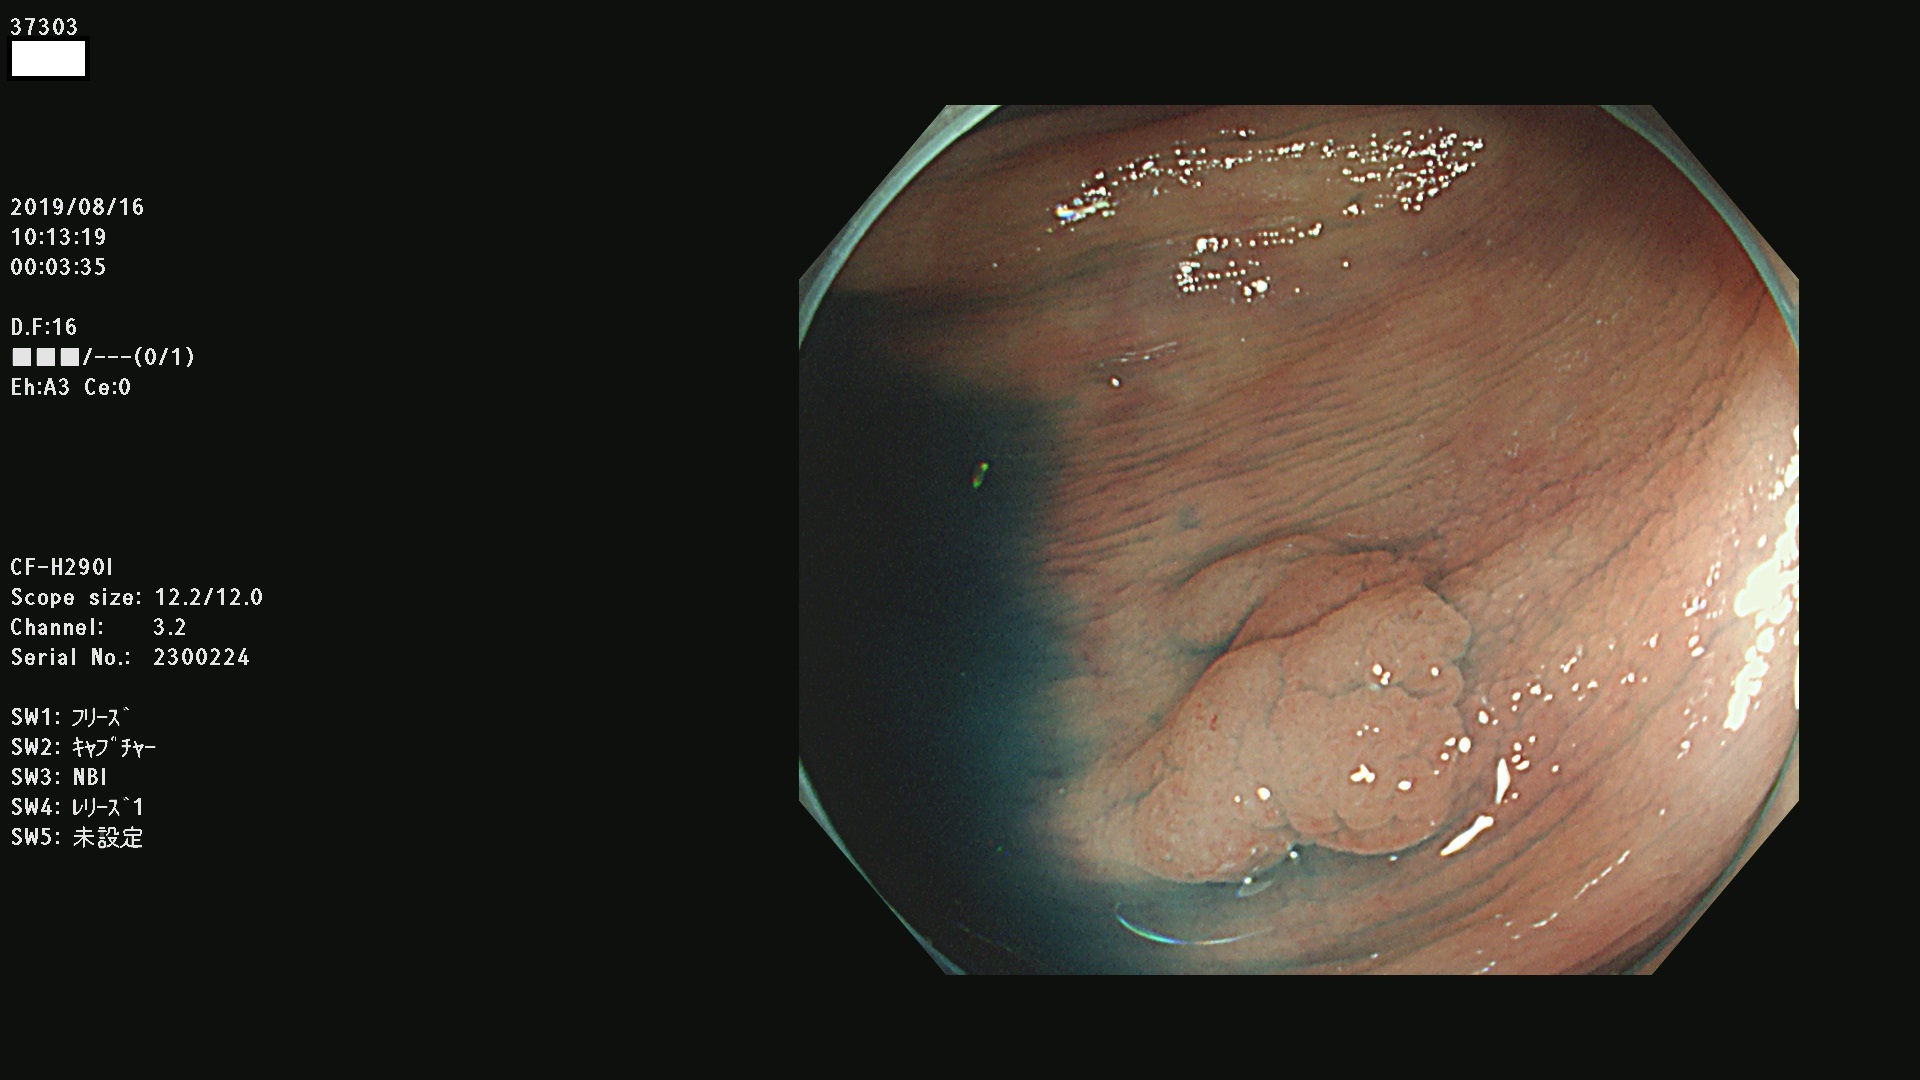

37300(SSAPのみ) 37301 37303 37304 37306 37307 37308 37309 37312 37313 37315(SSAPのみ) 37316 37317(SSAPのみ) 37319 37321(SSAPのみ) 37322 37323 37324 37325 37326 37328(SSAPのみ) 37329 37330 37331 37332(SSAPのみ) 37333 37334 37336 37337 37338 37340 37342 37343(SSAPのみ) 37344 37345 37346 37347 37348 37352(SSAPのみ) 37353 37354 37355 37356 37358 37360 37361(SSAPのみ) 37362 37363 37366 37367 37369 37370 37371 37372(SSAPのみ) 37375 37376 37377 37380 37381(SSAPのみ) 37382 37383 37384 37385(SSAPのみ) 37386 37387 37388 37389 37390 37392(SSAPのみ) 37393 37394 37395 37396(SSAPのみ) 37397 37398(SSAPのみ) 37399

発見困難で危険性の高い平坦型病変(上記100名より抽出) )